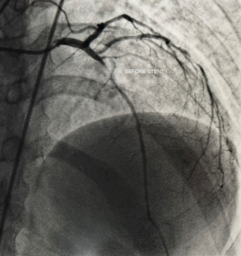

Cardiac catheterization procedure performed in a specialized hospital lab.

- During the procedure, a thin flexible tube (catheter) is inserted through an artery in the wrist or groin and guided to the heart. A colorless contrast dye is injected, allowing detailed X-ray images to show whether any coronary arteries are narrowed or blocked, and the exact location and severity of the blockage.

Angiogram showing detailed images of the coronary arteries and areas of narrowing.